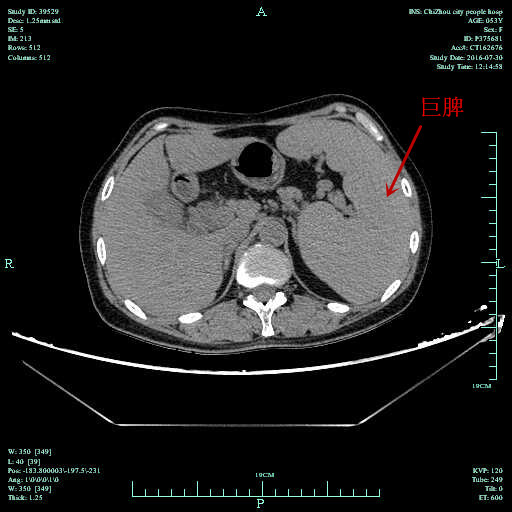

近期,普外科肝胆病区成功完成一例腹腔镜下胆道探查联合巨脾切除术,患者已痊愈出院。

患者为53岁女性,因胆总管结石、胆囊结石收住院,术前检查发现合并有巨脾伴脾功能亢进,均需手术治疗。由于手术部位分属于左右上腹部,如一次手术则需在左右上腹部各开一大切口,创伤过大,既往多选择分次手术。经科室讨论后,8月4日由孔胜兵主任医师主刀,利用腹腔镜视野清晰、操作范围广的优势,同时完成了胆囊切除、胆总管切开取石、T管引流及脾切除术,巨大脾脏破碎后经脐缘小切口取出,术后腹部仅留下几个钥匙孔大小切口及脐缘约5cm小切口,患者恢复快、疼痛轻、住院时间短。